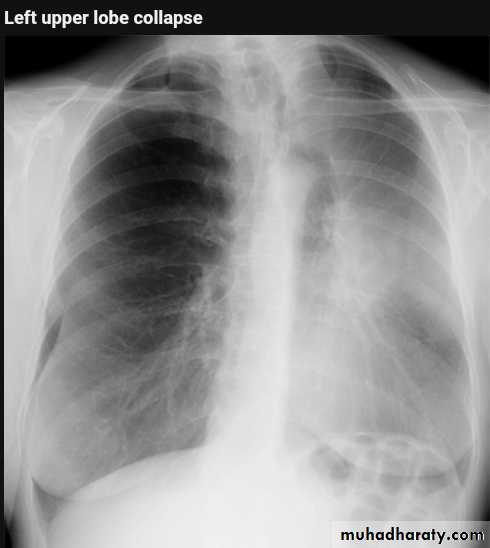

Left upper lobe collapse has distinctive features but can be challenging to identify on chest radiographs by the uninitiated.

Radiographic features

The left upper lobe collapses anteriorly becoming a thin sheet of tissue apposed to the anterior chest wall, and appears as a hazy or veiling opacity extending out from the hilum and fading out inferiorly . It thus reverses the normal slight increase in radiographic density seen as you move down the lung (due to increased thickness of the chest soft tissues).

Parts of the normal cardiomediastinal contour may also be obliterated where the left upper lobe, particularly the lingula abut the left heart border. The anterior parts of the aortic arch are also often obliterated from view.

In some cases the hyperexpanded superior segment of the left lower lobe insinuates itself between the left upper lobe and the superior mediastinum, sharply silhouetting the aortic arch and resulting in a lucency medially. This is known as the luftsichel sign.

The left hilum is also drawn upwards, resulting in an almost horizontal course of the left main bronchus and vertical course of the left lower lobe bronchus.

Non-specific signs indicating left sided atelectasis will also be present, including:

elevation of the hemidiaphragm

'peaked' or 'tented' hemidiaphragm: juxtaphrenic peak sign

crowding of the left sided ribs

shift of the mediastinum to the left

On lateral projections the left lower lobe is hyperexpanded and the oblique fissure displaced anteriorly. There is associated increase in the retrosternal opacity.